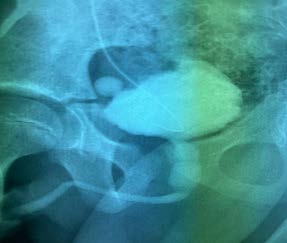

Figura 2. Recién nacida con diagnóstico intraútero de hidronefrosis bilateral, UCGM demuestra RVU grado IV bilateral.

Fuente: PACS-Hospital Metropolitano de Quito-2021.

Nuestro estudio demuestra una prevalencia alta en relación al total de pacientes estudiados tomando en cuenta nuestra muestra, presentándose en varones con una prevalencia de 9,37% 6 pacientes de un total de 64, en relación a las mujeres que presentaron una prevalencia de RVU de 19,35 % que corresponde a 18 pacientes de un total de 93 (Figuras 2 y 6), existiendo una concordancia con el estudio realizado por Dr. Díaz M, Dra. Acosta et al., Argentina 2009, donde se encontró una prevalencia de 20,9% (75/358)9.